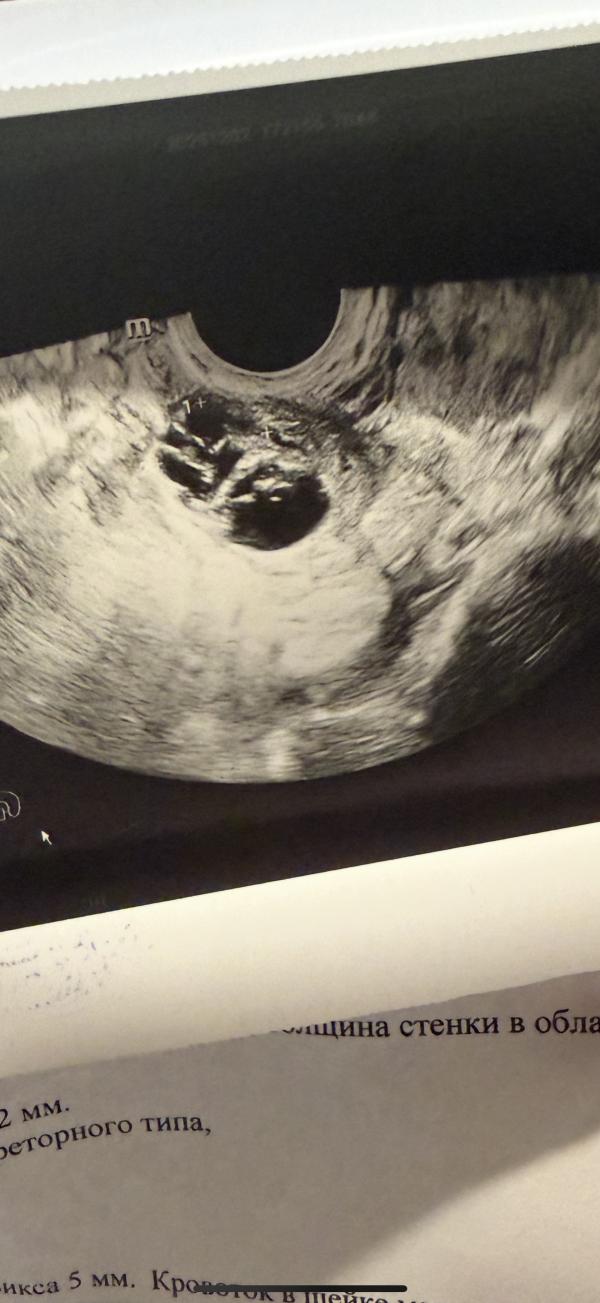

26.11 - 42.9

28.11 - 111.6

02.12 - 799.4

17 декабря на узи, будет около 6.3 недели